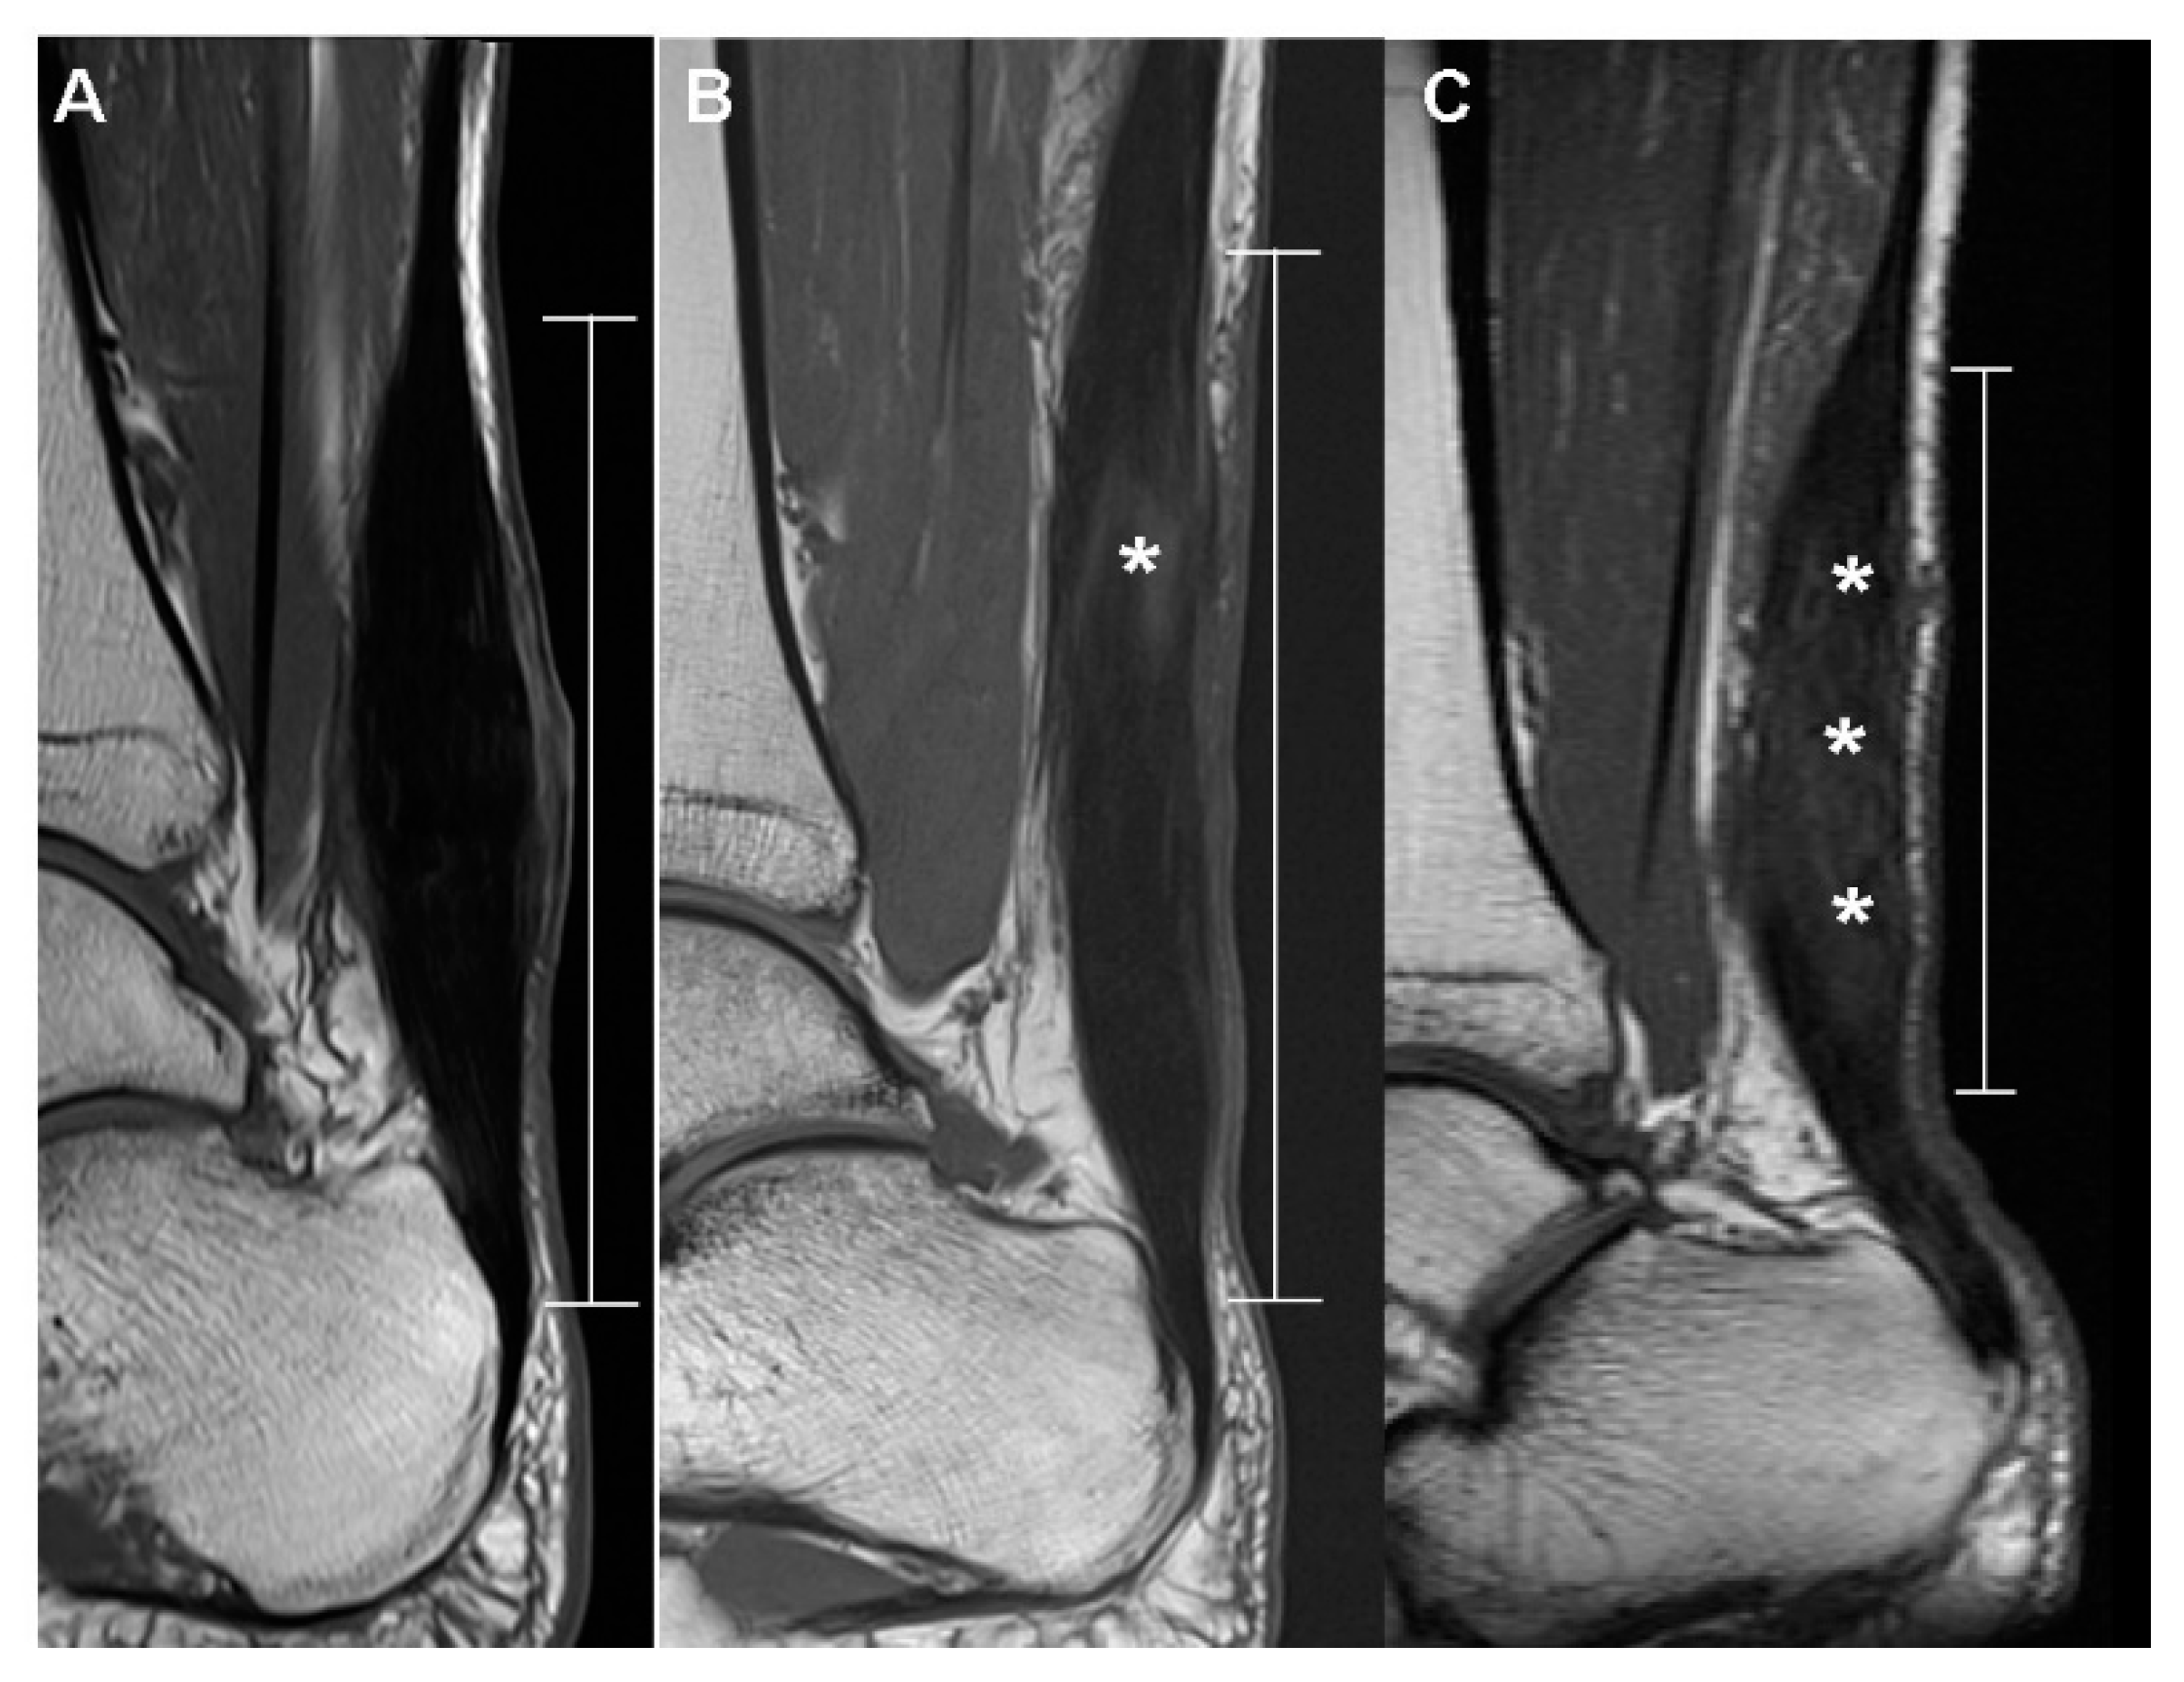

2.5.1. T1-Weighted Sagittal Image

| Postop appearance | 0.0789 | ||

| Diffusely isointense thickened | 5 (45.45%) | 1 (9.1%) | |

| Diffusely elongated | 3 (27.27%) | 2 (18.2%) | |

| Focally fusiform | 3 (27.27%) | 8 (72.7%) | |

| Dark SI artifact | 0.0063 | ||

| None | 3 (27.27%) | 0 (0%) | |

| Mild | 8 (72.73%) | 5 (45.5%) | |

| Marked | 0 (0%) | 6 (54.5%) | |